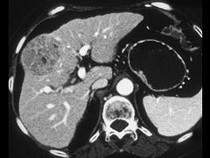

问题 女,55岁,右上腹痛,消瘦乏力3个月,请结合图像诊断为()

选项 A.肝血管瘤 B.肝腺瘤 C.肝癌 D.肝脓肿 E.肝转移癌

答案 C